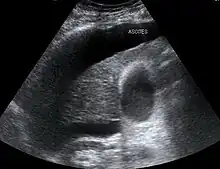

Both types of hepatorenal syndrome share three major components: altered liver function, abnormalities in circulation, and death. As these phenomena may not necessarily produce symptoms until late in their course, individuals with hepatorenal syndrome are typically diagnosed with the condition on the basis of altered laboratory tests. Most people who develop HRS have cirrhosis, and may have signs and symptoms of the same, which can include jaundice, altered mental status, evidence of decreased nutrition, and the presence of ascites.[2] Specifically, the production of ascites that is resistant to the use of diuretic medications is characteristic of type 2 HRS. Oliguria, which is a decrease in urine volume, may occur as a consequence of kidney failure; however, some individuals with HRS continue to produce a normal amount of urine.[3] As these signs and symptoms may not necessarily occur in HRS, they are not included in the major and minor criteria for making a diagnosis of this condition; instead HRS is diagnosed in an individual at risk for the condition on the basis of the results of laboratory tests, and the exclusion of other causes.[3]